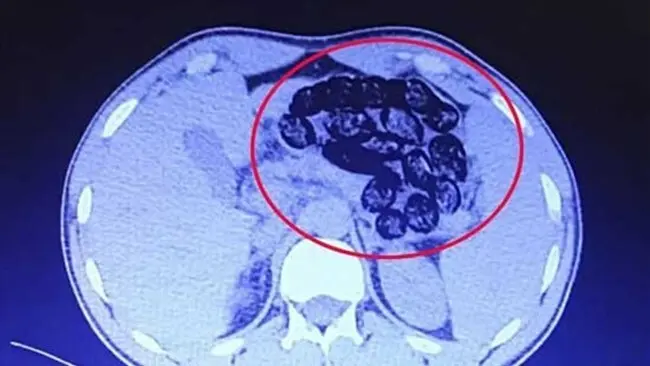

در ادامه این اطلاعیه آمده: بر اساس توضیحات مأمور همراه، این فرد پیش از ورود به بیمارستان، اقدام به بلع چندین بسته محتوی مواد مخدر کرده بود و در تصویربرداری‌های انجام‌شده، مشخص شد تعداد قابل‌توجهی بسته درون معده و روده‌های کوچک و بزرگ او شناسایی شد.

بعد از عمل جراحی مشخص شد این فرد میانسال ۹۰ بسته مواد مخدر را بلعیده است.